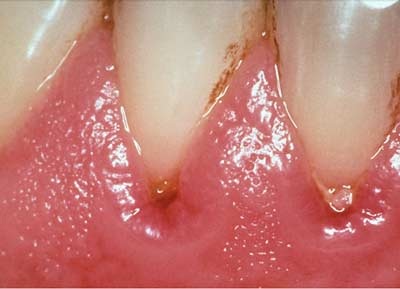

Ngăn ngừa viêm lợi bằng chải răng và chỉ tơ nha khoa

Không điều trị viêm lợi sẽ dẫn tới các bệnh bao quanh chân răng